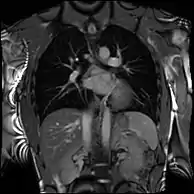

Example CMR images. In sequence: a coronal localiser, 2 chamber cine, 4 chamber cine, left ventricular short axis cine, and tagged image. Additional cines of the left ventricular outflow tract and aortic valve may also be acquired.